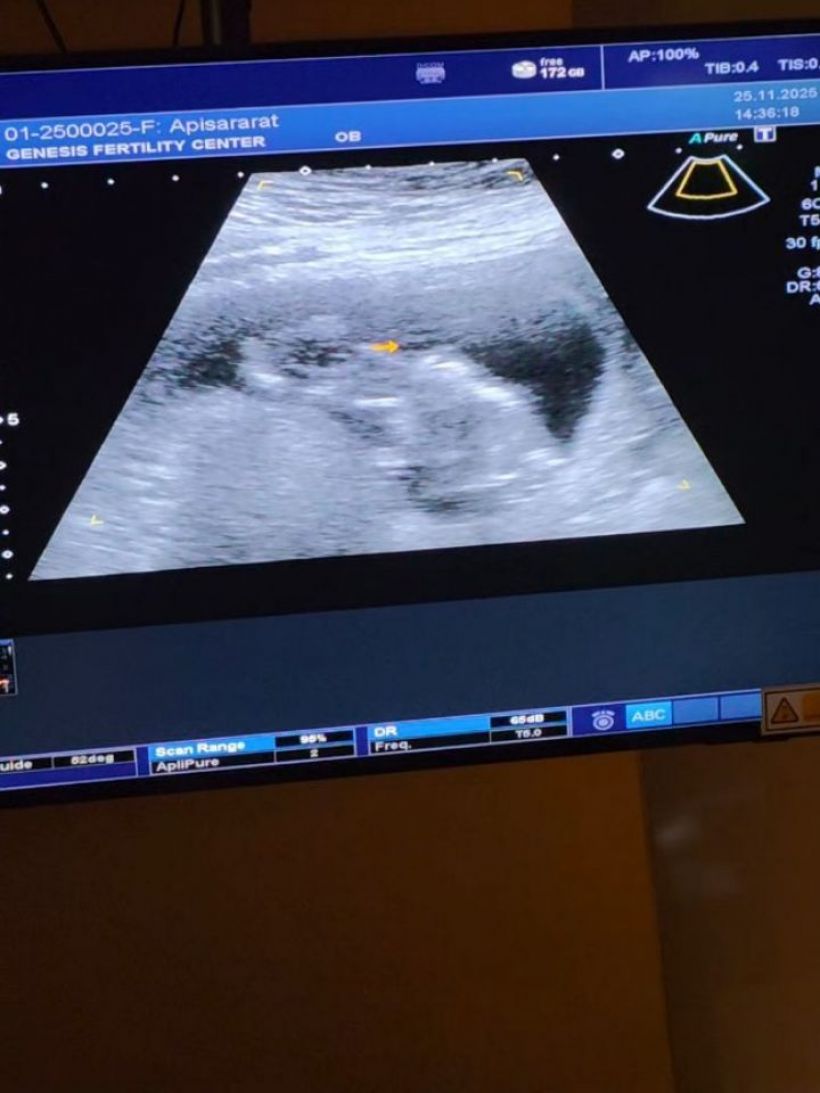

จนกระทั่งล่าสุดวันนี้ (28 พ.ย.) ลีซอ โพสต์ IG @leesawls14 เผยภาพอัลตร้าซาวด์เบบี๋ พร้อมเผยว่า "Finally วันนี้ก็มาถึง!!

คนที่มีบุตรยากอย่างเรา2คน วันนี้เราอยากจะบอกข่าวดีเบื้องต้นกับหลายๆคนที่ลุ้นและตื่นเต้นไปพร้อมกับพวกเราในการมีเบบี๋ตัวน้อย วันนี้เรามีเจ้าตัวน้อยนักสู้แบบผมมาแล้ว เย้ๆ ตอนนี้เฟียตตั้งครรภ์ได้12สัปดาห์แล้วครับ เป็นการใส่ตัวอ่อนครั้งแรกก็ติดเลย เก่งมากทั้งแม่และลูกแดดดี๊เลย แต่กว่าจะใส่ตัวอ่อนได้ เราเก็บไข่กันมาถึง5รอบ กว่าจะมีตัวอ่อนทองคํา เพียงหนึ่งเดียว เราต้องผ่านการอดทนและปัจจัยอีกหลายอย่างมาก" ท่ามกลางคนบันเทิงและแฟนคลับร่วมแสดงความยินดีล้นหลาม